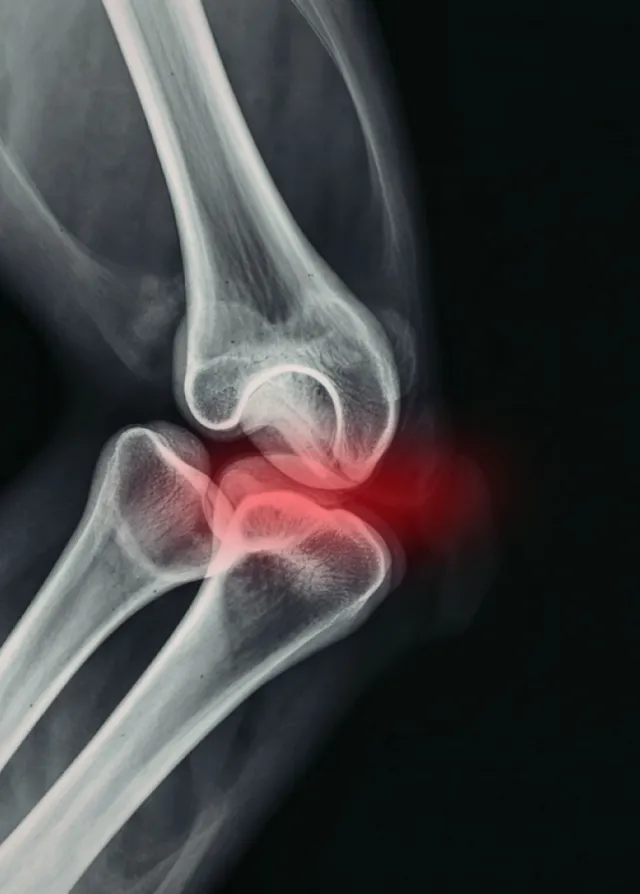

La rhumatologie est la spécialité médicale dédiée au diagnostic, au traitement et au suivi des affections de l’appareil locomoteur, incluant les articulations, les os, les muscles, les tendons et la colonne vertébrale. Elle concerne aussi bien les pathologies inflammatoires, dégénératives que les troubles musculo-squelettiques chroniques ou aigus.

La rhumatologie prend en charge un large éventail de pathologies, parmi lesquelles :

L’arthrose

Les rhumatismes inflammatoires chroniques (polyarthrite rhumatoïde, spondylarthrite, rhumatisme psoriasique)

Les pathologies inflammatoires microcristallines (goutte, chondrocalcinose articulaire, etc.)

- examens d’imagerie (radiographies, IRM, scanner, échographie ostéo-articulaire) ;